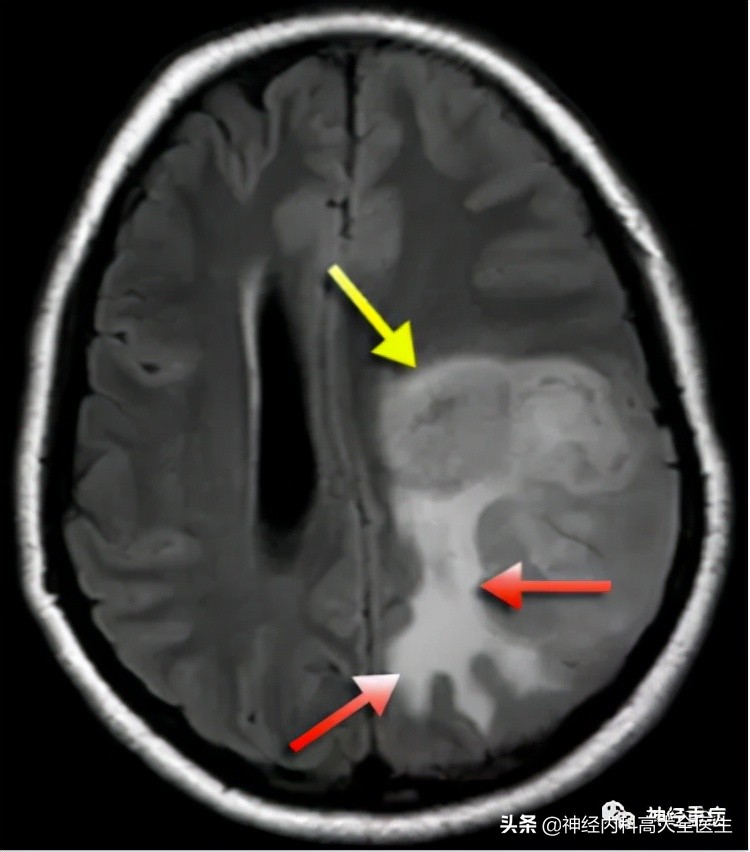

典型疾病如脑肿瘤、脑脓肿、脑炎: